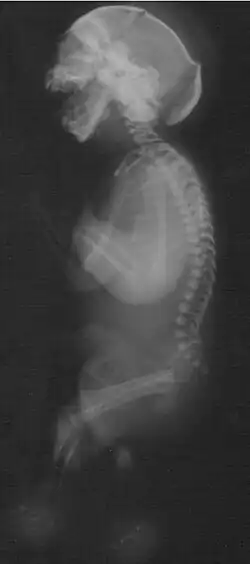

Babygram of stillborn baby with Neu-Laxova syndrome (same case)[1]

Neu-Laxova syndrome presents with severe malformations leading to prenatal or neonatal death. Typically, NLS involves characteristic facial features, decreased fetal movements and skin abnormalities.[5] Fetuses or newborns with Neu–Laxova syndrome have typical facial characteristics which include proptosis (bulging eyes) with eyelid malformations, nose malformations, round and gaping mouth, micrognathia (small jaw) and low set or malformed ears. Additional facial malformations may be present, such as cleft lip or cleft palate. Limb malformations are common and involve the fingers (syndactyly), hands, or feet. Additionally, edema and flexion deformities are often present. Other features of NLS are severe intrauterine growth restriction, skin abnormalities (ichthyosis and hyperkeratosis) and decreased movement. Malformations in the central nervous system are frequent and may include microcephaly, lissencephaly or microgyria, hypoplasia of the cerebellum and agenesis of the corpus callosum. Other malformations may also be present, such as neural tube defects.